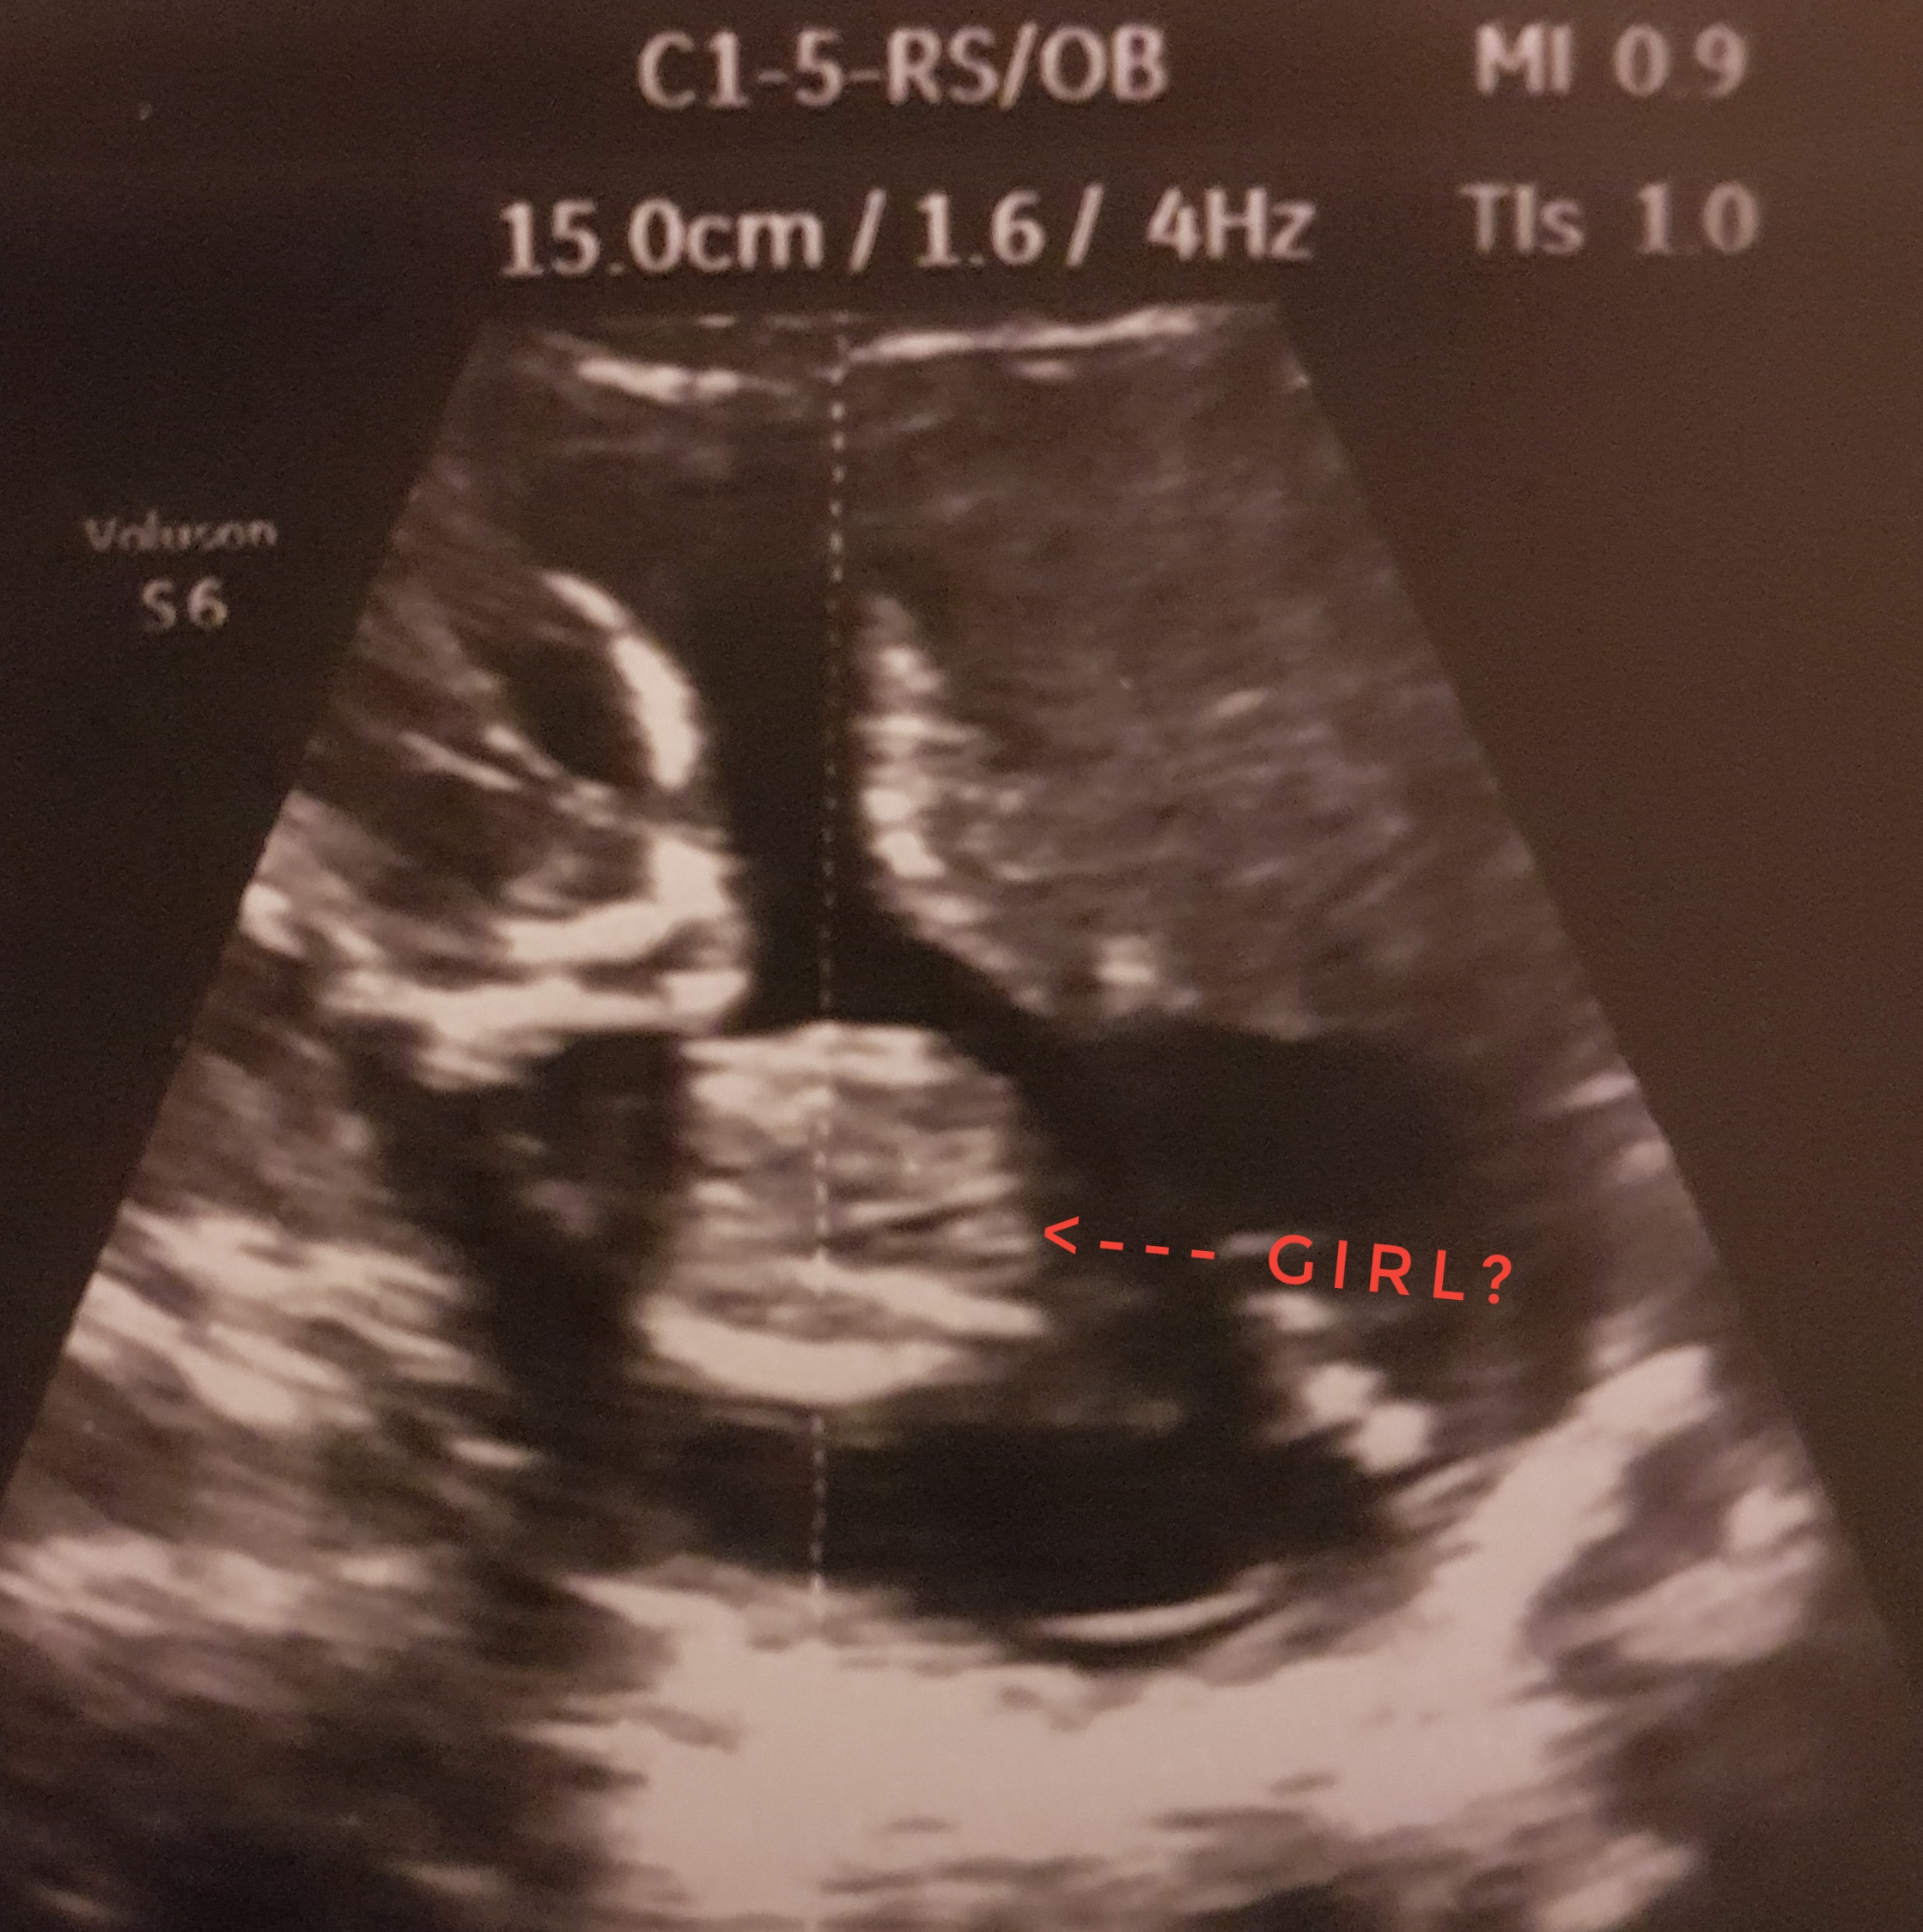

Thank you, pleas see these two more pics, maybe they gives more info, for me also not so clear.Attachment 40867

I want to add that after these 2 last shots dr wasn't 100% sure as well. I hope there is a hope:)

Attachment 40868

Your latest pics changed my mind, I'm going with a boy guess. It looks like a fairly obvious penis and scrotum in your newest pics. I'm sorry, I wish I could tell you otherwise.